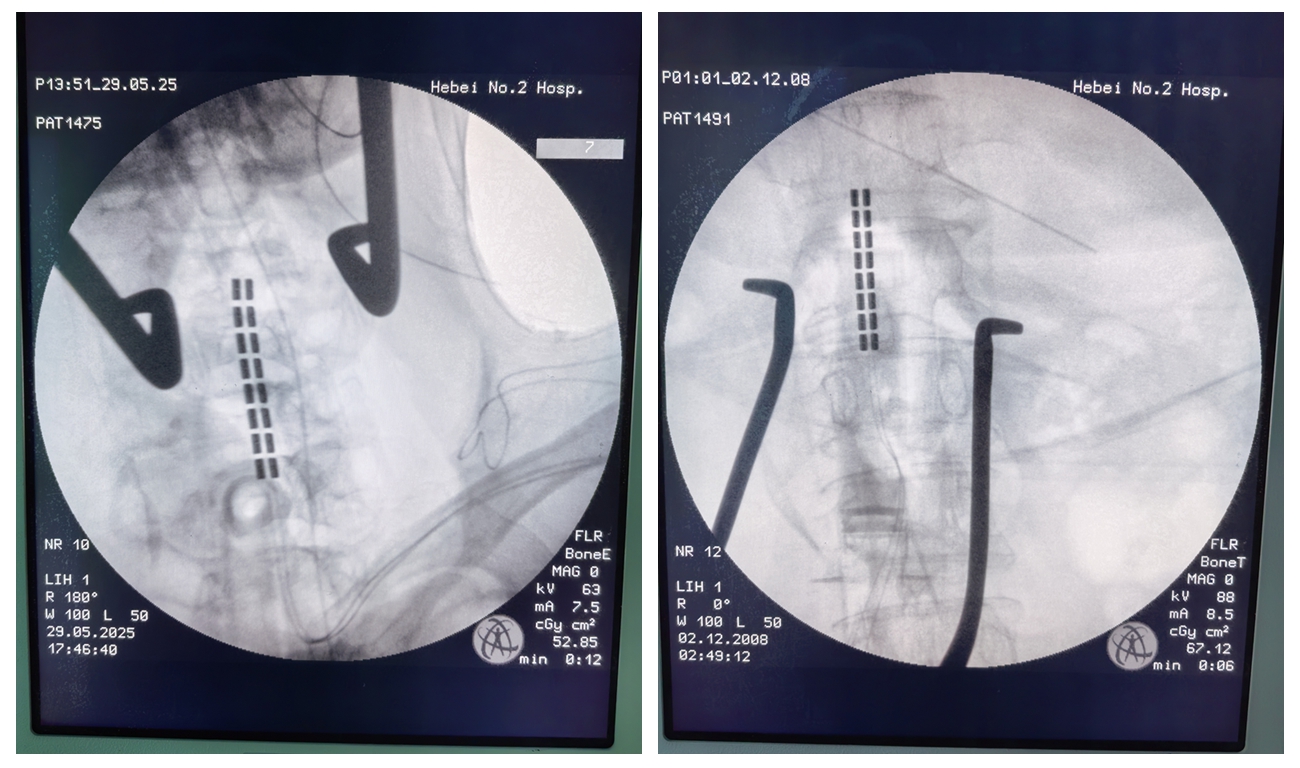

(颈椎电极;腰椎电极)

针对这一难题,神经外科团队为其分阶段实施了脊髓电刺激术。该技术通过在脊髓硬膜外放置电极,发放特定脉冲,调节脊髓神经网络,从而抑制过度兴奋的运动神经元,缓解肌张力增高。

治疗首先进行了为期三周的试验性刺激。经影像引导精准放置电极后,给予交替频率的电刺激。期间患者痉挛程度显著减轻,夜间痉挛发作减少70%以上,初步验证了该技术的有效性。